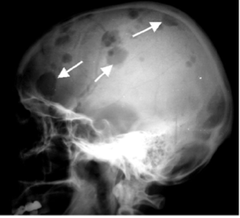

Front

-CLASSIC TRIAD: skull radiolucencies, exopthalmos, diabetes insipidus -Oral: sore mouth with or without ulceration, halitosis, gingivitis, unpleasant taste, loose/sore teeth -children under 5